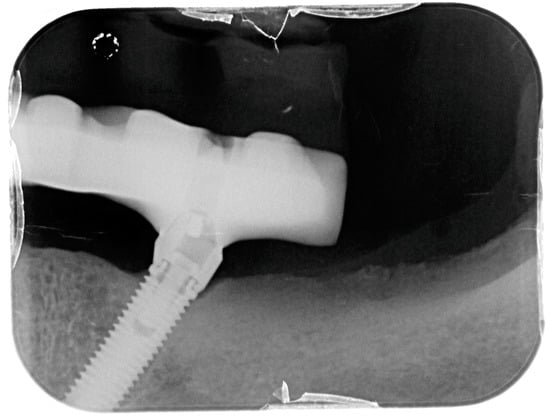

Figure 2.

X-ray of dental implant area before treatment.

X-ray of dental implant area after treatment.